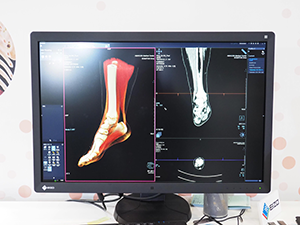

このほか,読影支援システムの「syngo.via」の新バージョンも紹介された。最新の“VB20”では,研究用の「syngo.via Frontier」でのみ可能であった“Cinematic Rendering”が可能となり,新たに“Cinematic VRT”として提供される。

syngo.viaに搭載されるCinematic VRT |